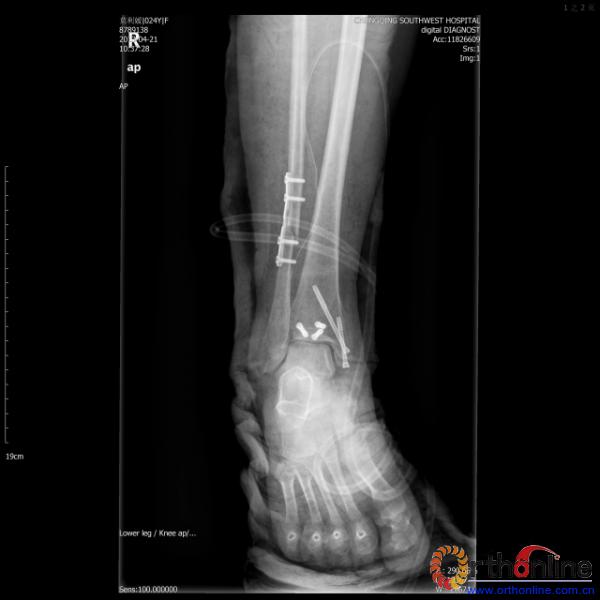

伤员和家属迅速赶到西南医院,10点关节外科段小军副教授查看伤员后急诊收入院,拍摄X片和急诊行三维CT重建检查,提示踝关节创伤严重,出现三踝骨折伴胫距关节脱位,需要急诊手术治疗。随后段教授与正在四川成都参加“汶川地震5周年灾害医学救治研讨会”的杨柳主任联系,进一步完善救治方案。地震当晚,段教授为该伤员进行急诊手术,手术顺利对复杂骨折进行了解剖复位,有效的钢板螺钉固定。术后伤员的疼痛明显缓解,复查X片,踝关节结构恢复满意。

患者术后X片(一)